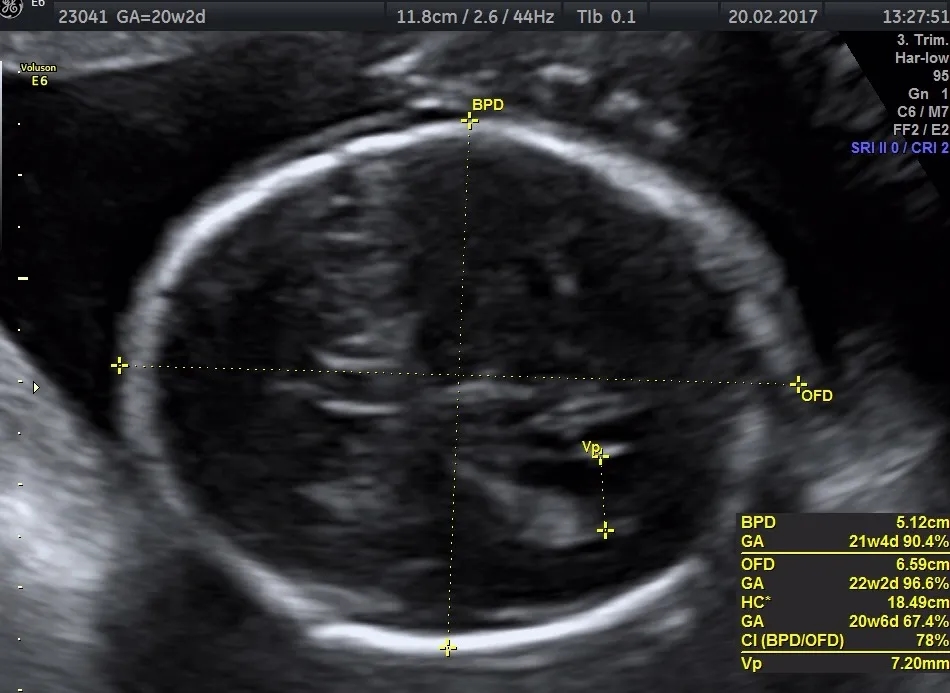

Co obejmuje badanie połówkowe? Kluczowe aspekty procedury

Badanie połówkowe to nie tylko ocena budowy płodu, ale również analiza wielu istotnych parametrów. USG w ciąży pozwala na sprawdzenie położenia płodu, dojrzałości łożyska oraz ilości wód płodowych. To drugie z obowiązkowych badań, które dostarcza cennych informacji o rozwoju dziecka.

Podczas tego badania lekarz ocenia także struktury anatomiczne płodu, co pozwala na wczesne wykrycie ewentualnych nieprawidłowości. Badania prenatalne mają na celu zapewnienie bezpieczeństwa zarówno matce, jak i dziecku, a ich znaczenie jest nie do przecenienia.

Jakie informacje można uzyskać z badania ultrasonograficznego?

Badanie połówkowe dostarcza wielu cennych informacji o zdrowiu płodu. USG w ciąży pozwala na ocenę budowy ciała dziecka oraz jego funkcji życiowych. W trakcie tego badania lekarze mogą zidentyfikować ewentualne wady rozwojowe i ocenić, czy płód rozwija się prawidłowo.